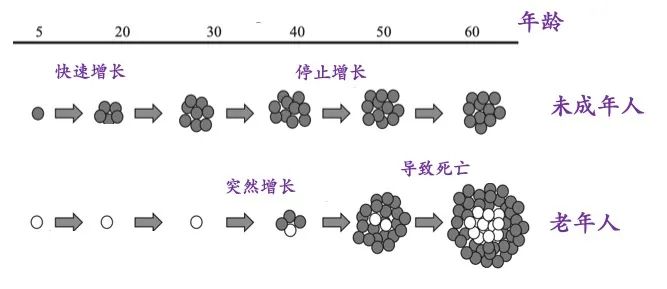

懒癌会复发吗? 甲状腺癌是最为常见的一种内分泌恶性肿瘤,近10年来,其发病率在全球持续快速上涨。约95%的甲状腺癌为分化型甲状腺癌 ( differentiated thyroid cancer,DTC) ,也就是俗称的“懒癌”,主要包括甲状腺乳头状癌( papillary thyroid carcinoma,PTC) ,甲状腺滤泡状癌( follicular thyroid carcinoma,FTC) 和嗜酸细胞癌( Hürthle cell carcinoma,HCC) 。 分化型甲状腺癌(DTC)的长期预后非常好,在10年随访中,成人DTC患者的生存率为92-98%。然而,5%-20%的患者出现局部或区域复发,复发时间从6个月至数十年不等,10-15%的患者继续发展为远处转移。甲状腺床和颈部淋巴结是DTC患者最常见的局部或区域复发部位,而远处转移主要见于肺和骨骼。

复发风险分层以术中病理特征、淋巴结转移特征、分子病理特征及TSH刺激后(TSH>30mU/L)Tg(sTg)水平和131I 治疗后全身扫描(post-treatment whole body scan,Rx-WBS)等权重因素将患者的复发风险分为低、中、高危三层。利用这一分层系统指导是否对DTC患者进行131I治疗,以降低或控制复发风险。